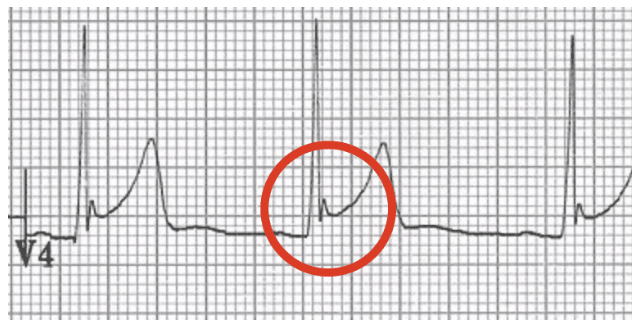

Question 6 of 7

This is commonly seen with what condition:

A

HCM

B

WPW

C

Benign early repolarization

D

STEMI